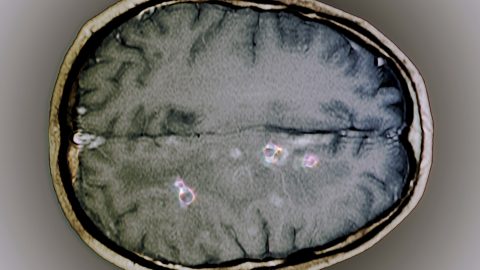

Az egyik amerikai elnökjelölt állítja: agyának egy részét megette egy féreg – Vajon tényleg megtörténhet ilyesmi?

Ma már semmin sem lepődünk annak kapcsán, mi mindent hordanak össze a politikusok, ha az érdekük úgy kívánja. De azért az elég bizarr, ha valaki azzal áll elő, hogy az agyát egy féreg rágta meg. Mit kezdjünk a dologgal, ha ilyet hallunk? Higgyük el?